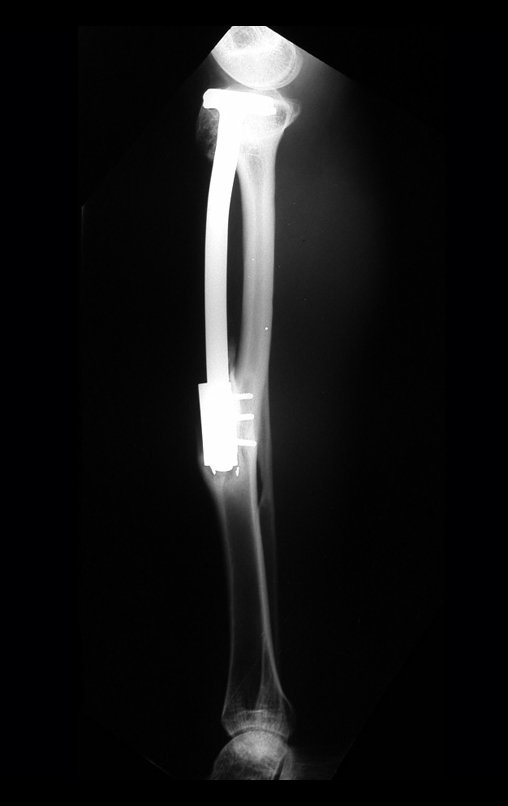

Miembro inferior alineado y clínicamente con la pierna más corta, ya que el acortamiento se produjo desde el inicio, debido a la inclinación de la epífisis, provocando deslizamiento inferior del vástago de la placa, ya demostrado con la inclinación de los tornillos epifisarios.

Han pasado diez años desde la evaluación de 2005. El paciente, que ahora tiene 28 años, regresa el 15 de noviembre de 2015. Actualmente trabaja como conductor, transportando azúcar a granel desde el estado de Minas Gerais hasta el puerto de Santos. Recorre 800 kilómetros conduciendo un camión, utilizando su pierna derecha para acelerar y frenar. La reconstrucción de la pierna, realizada con autotrasplante de cartílago de crecimiento, resulta ser una excelente alternativa a las endoprótesis para niños en crecimiento, con buenos resultados funcionales. Una solución biológica, autóloga y definitiva.